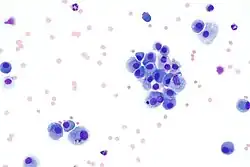

Blood film with Giemsa stain. White blood cells (center) surrounded by red blood cells.

Romanowsky staining, also known as Romanowsky–Giemsa staining, is a prototypical staining technique that was the forerunner of several distinct but similar stains widely used in hematology (the study of blood) and cytopathology (the study of diseased cells). Romanowsky-type stains are used to differentiate cells for microscopic examination in pathological specimens, especially blood and bone marrow films,[1] and to detect parasites such as malaria within the blood.[2][3][4][5] Stains that are related to or derived from the Romanowsky-type stains include Giemsa, Jenner, Wright, Field, May–Grünwald and Leishman stains. The staining technique is named after the Russian physician Dmitri Leonidovich Romanowsky (1861–1921), who was one of the first to recognize its potential for use as a blood stain.[6]